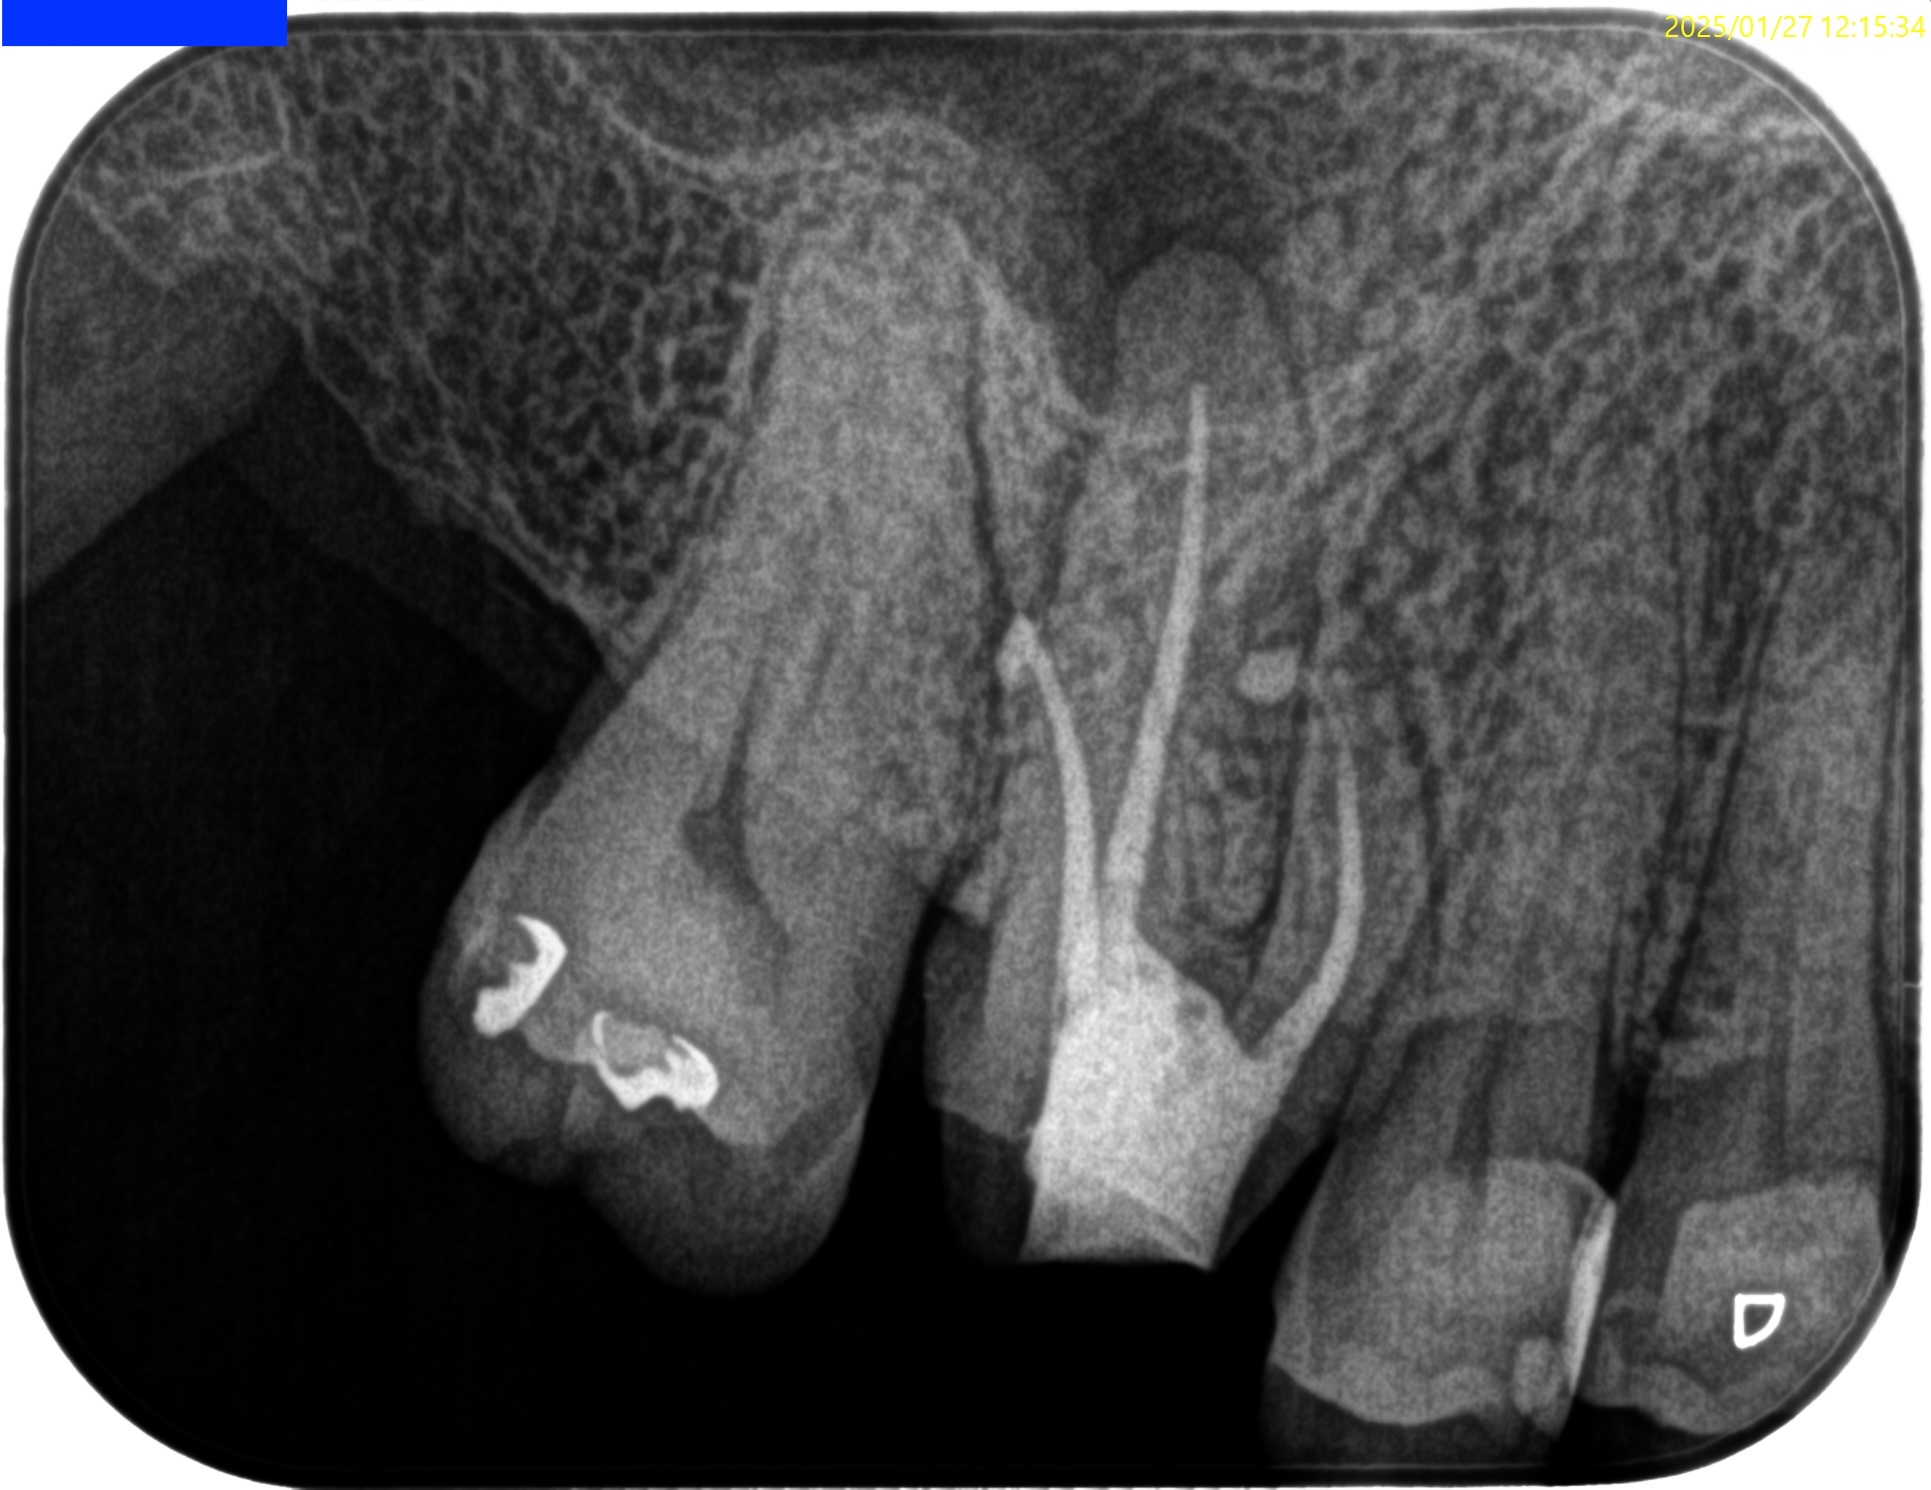

#3 RCT(2025.1.27)

PがUnderextensionの根充のような印象を与える…

が、時間が経過しないと治癒するか否かはわからない。